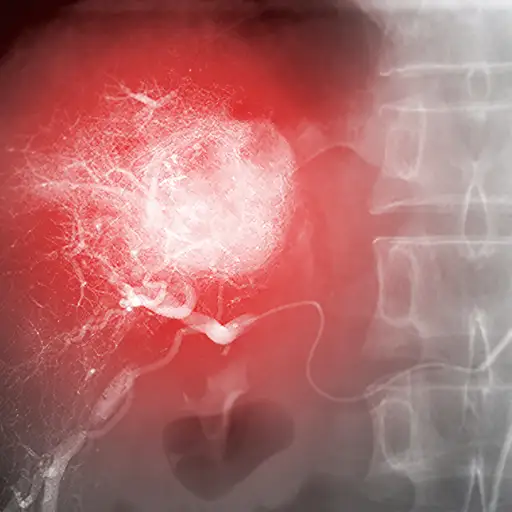

第4阶段:治疗转移

根据癌细胞扩散的位置,你可能需要其他特定的治疗方案来靶向转移。如果癌症已经扩散到肝脏,这在结肠癌中很常见,有时需要消融或栓塞来移除它。这包括注射一种物质来阻止血液流向肿瘤,或者使用热、冷或射频来杀死肿瘤。阿尔博博士说:“它在到达肿瘤的过程中,没有破坏你不想破坏的东西。”和化疗一起,这可以帮助清除扩散到结肠以外的癌细胞。